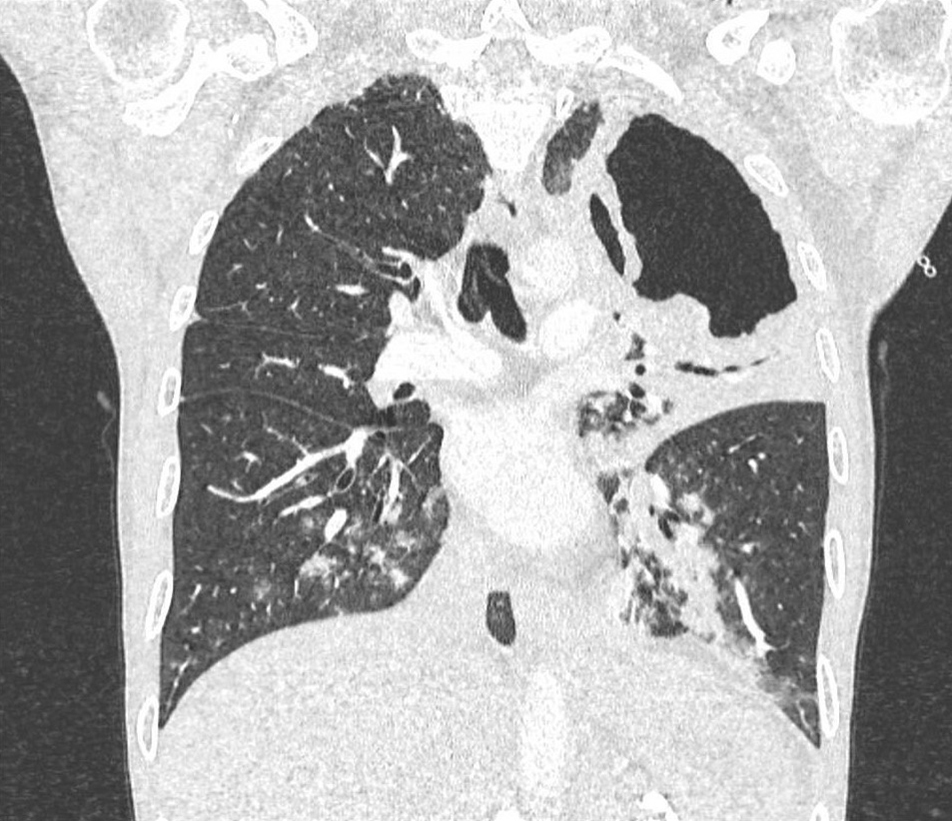

Il s’agit d’un scanner du thorax en coupe frontale et en fenêtre parenchymateuse. On ne retrouve pas d’embolie pulmonaire mais on observe une lésion excavée lobaire supérieure gauche de grande taille avec une condensation alvéolaire péri-lésionnelle avec bronchogramme aérique. Dans les lobes inférieurs, il y a des micronodules centrés sur des bronches (distribution bronchogène ou en arbre en bourgeons).

Figure 2 (Ariane Amoura, La Revue du Praticien)

Question 2 - Quel est selon vous le diagnostic le plus probable à ce stade ?

Le diagnostic le plus probable devant l’altération de l’état général, le fébricule, le syndrome inflammatoire, la caverne située au lobe supérieur et les micronodules de distribution bronchogène dits en arbre à bourgeons est une tuberculose pulmonaire.